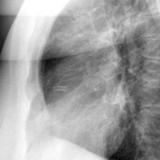

Ao valve calcif (lat only)

Date: 01/26/2009

Views: 2739